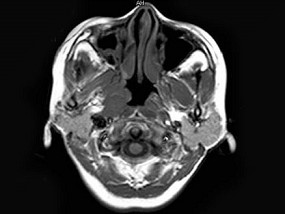

女,34岁。右侧听力下降,耳鸣2个月。MRI平扫及增强扫描如图示,最可能的诊断是 ( ) EBH-00871.jpg EBH-00872.jpg EBH-00873.jpg EBH-00874.jpg

• D.神经源性肿瘤